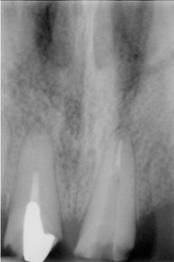

La nivelul lui 21 se observa obturatia de canal corect executata din punct de vedere radiologic. Clinic se constata obturarea canalului radicular cu ciment oxifosfat de zinc si fara con de gutaperca. Pe a doua radiografie se observa dezobturarea corecta a canalului radicular pt. realizarea unui DCR

La nivelul lui 12 si 13 se observa obturatia de canal corect executata din punct de vedere radiologic. Clinic se constata obturarea canalelor radiculare cu ciment oxifosfat de zinc si fara con de gutaperca. Pe a doua radiografie se observa dezobturarea corecta a canalelor radiculare pt. realizarea unor DCR-uri.